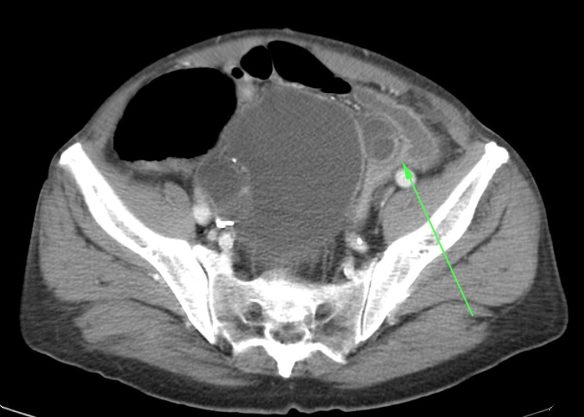

En el Scout se observa distensión de asas de colon y silencio radiológico en región teórica de colon descendente y sigma sin observar gas ni material fecal distal. Signos que con la clínica actual son compatibles con obstrucción intestinal.

Imagen radiologica:

El método de elección es la TC, ya que, si bien existen otras técnicas diagnósticas (como la radiografía simple, el enema de bario o la ecografía), ninguna presenta una sensibilidad y especificidad tan elevadas en la poblacion adulta.

- El hallazgo patognomónico es el signo de la escarapela o diana identificable en la TC o ecografía.

- Podemos ver la imagen de «Intestino dentro de intestino” gracias a las reconstrucciones multiplanares.